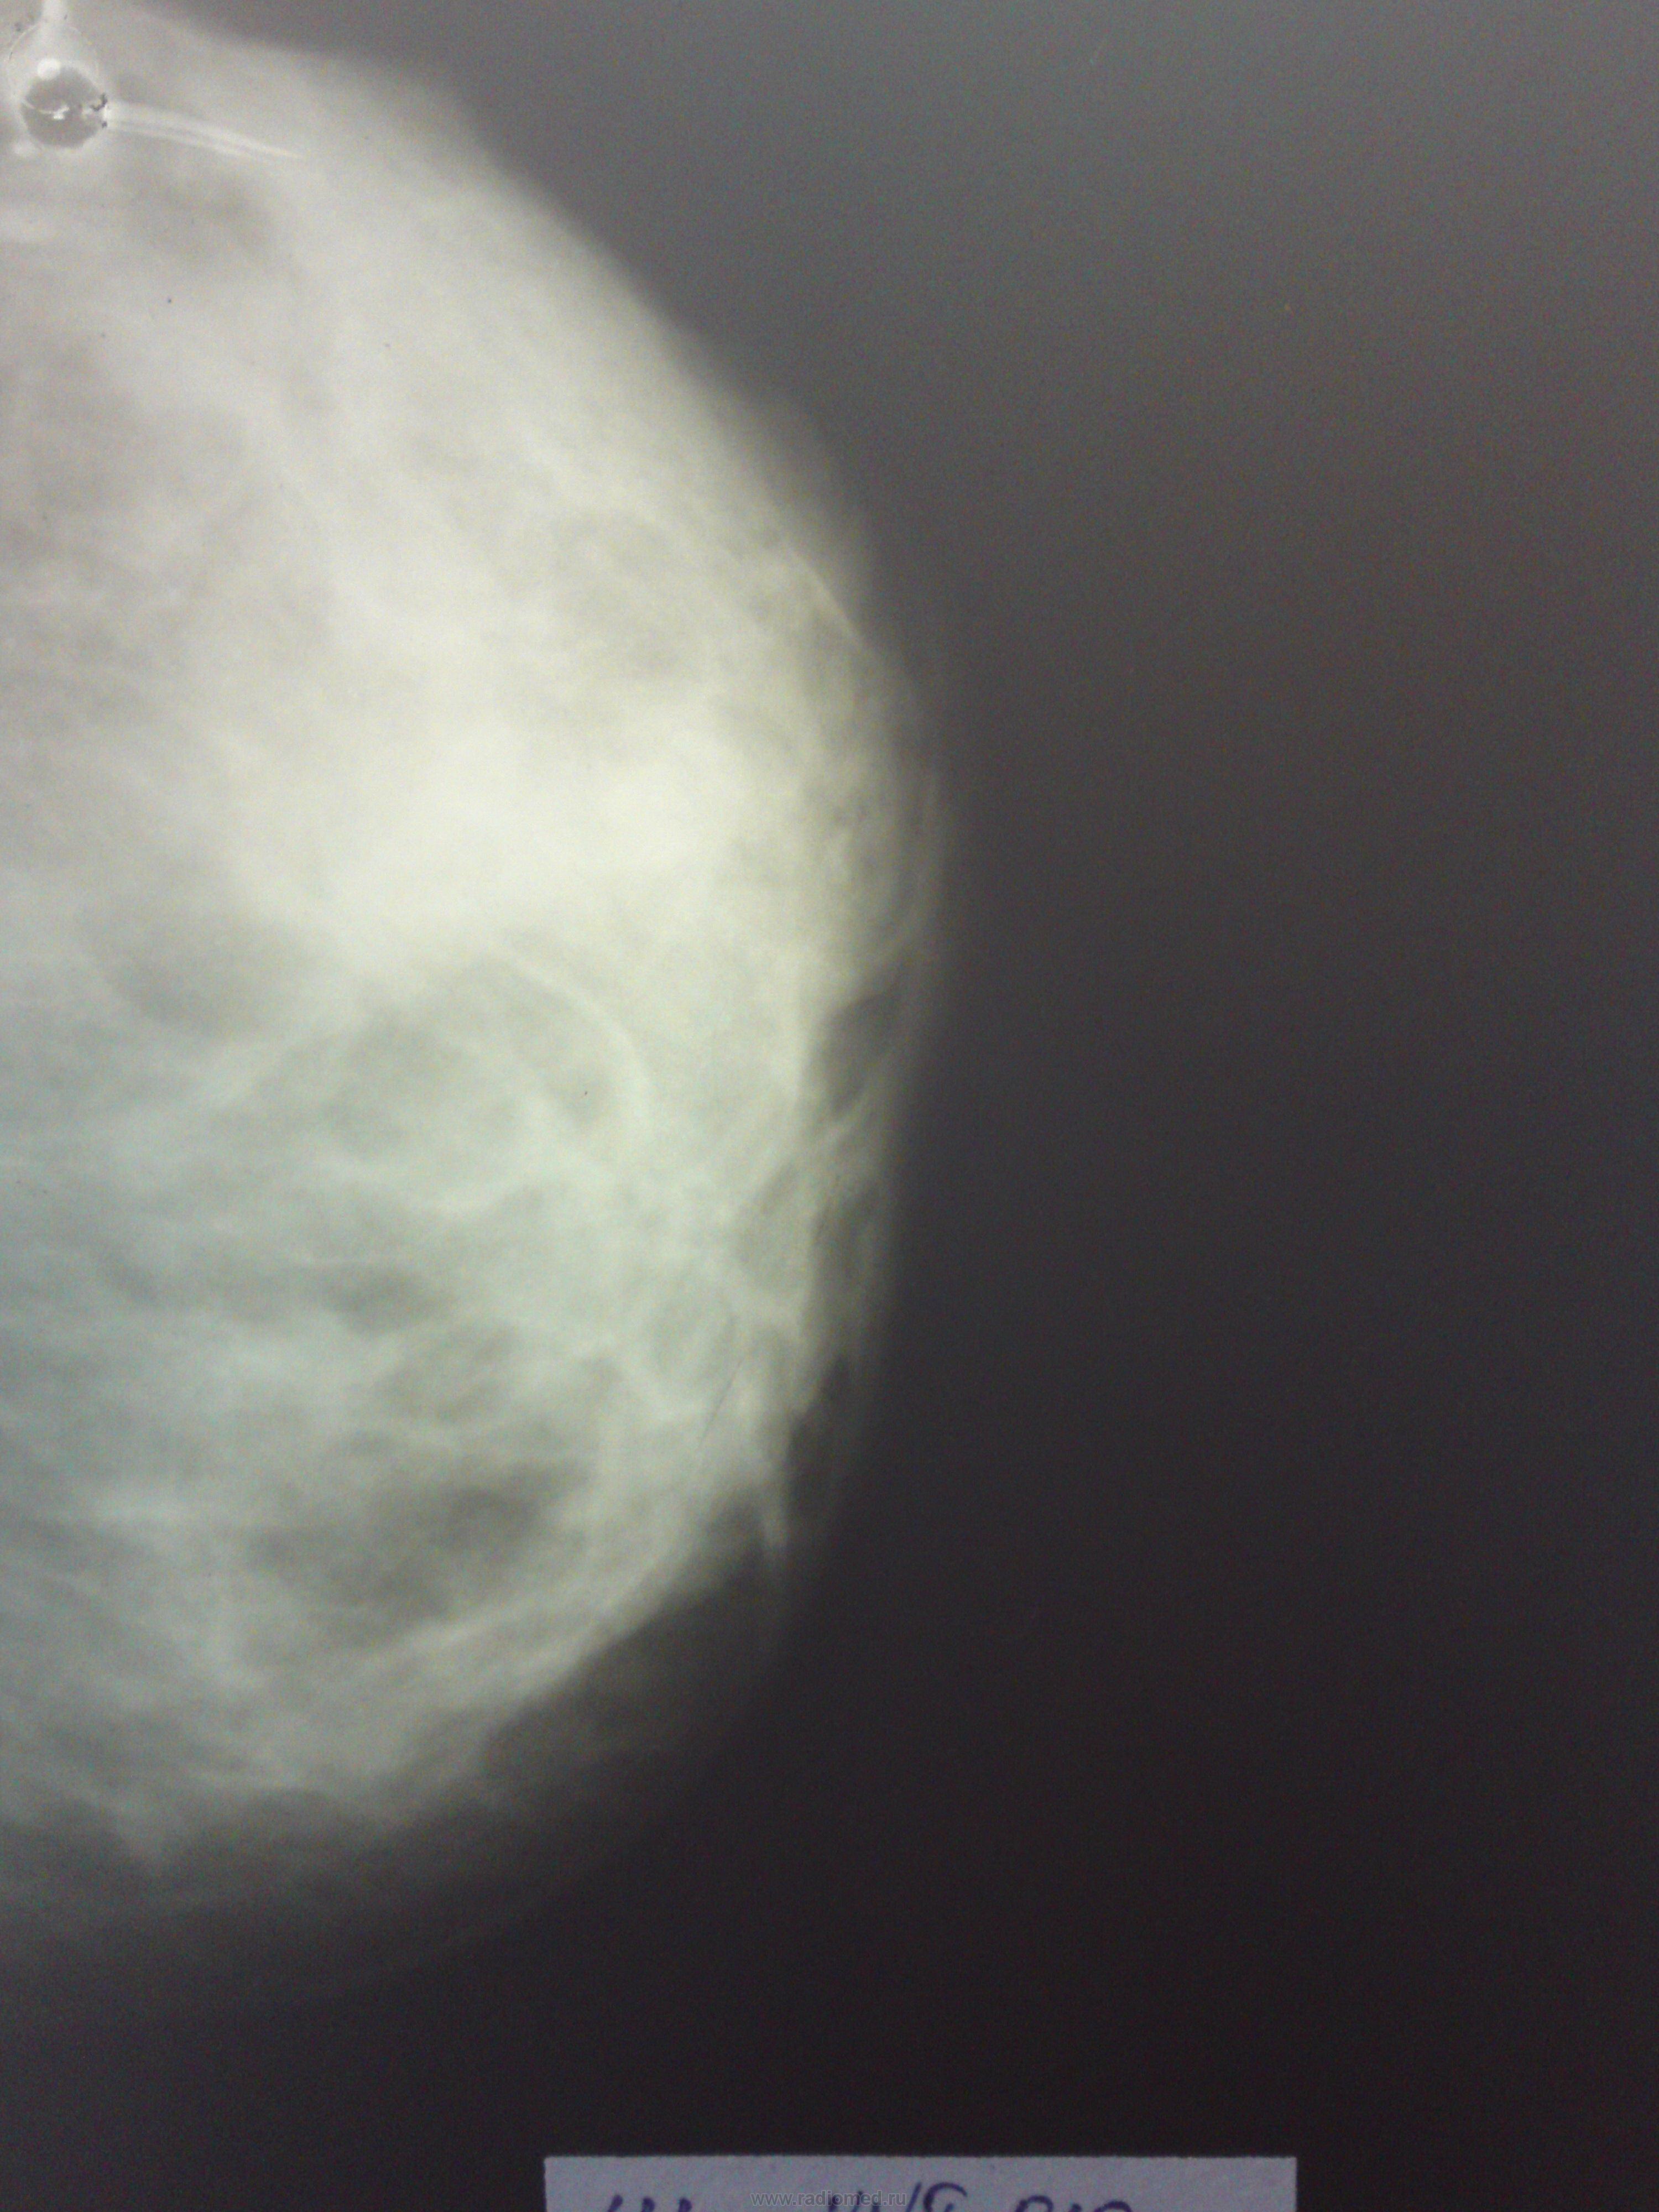

Маммография

Чуть не правильно расположил... А почему на косых нет грудной мышцы? Вижу пока только ДФКМ, направьте на УЗИ.. На левой косой в верхне наружном квадранте подозрительный участочек. Прицельные делаете?

Косых не делаем. Делаем боковые. В верхне-наружном квадранте имеется образования овоидной формы, больших размеров, с нечеткими контурами. А грудных мышц у нас почему-то никогда не видно...

слева в в/н квадранте видится округлое уплотнение очень трудно рассматриваемое, т.к.на "плотном" фоне(ДФКМ)  - узловая мастопатия?  нужна узи молочных желез

УЗИ сделано. Ставят Tumor